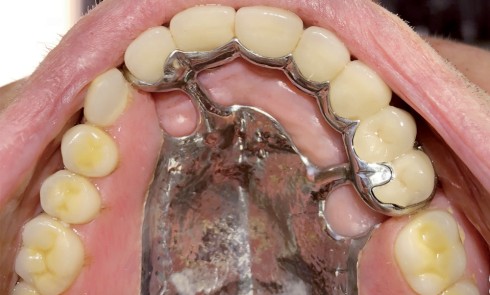

Article réservé à nos abonnés Prothèse amovible partielle combinée : à propos d’un cas clinique

L’apparition et la démocratisation de l’implantologie ont diminué les indications de PAP composite. Toutefois, dans certaines situations, conserver quelques dents...